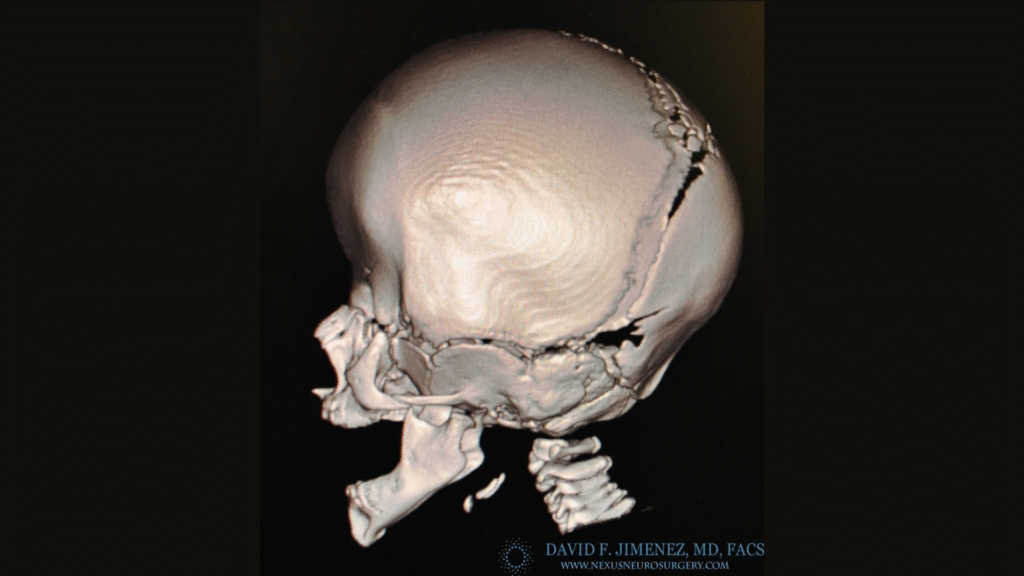

At El Paso Craniofacial Team, the primary treatment for craniosynostosis is surgery. First performed in the late 1800s, surgical approaches have continued to evolve and improve. The two main approaches are Calvarial Vault Remodel (CVR) and endoscopic-assisted surgery, with each tailored to the child’s age, the affected suture, and the severity of the condition.